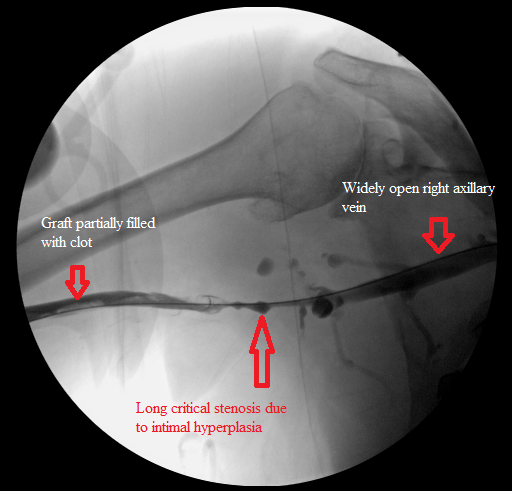

Long venous limb stenosis before dilation

Right arm venogram: long smooth brachial vein stenosis distal to the graft.